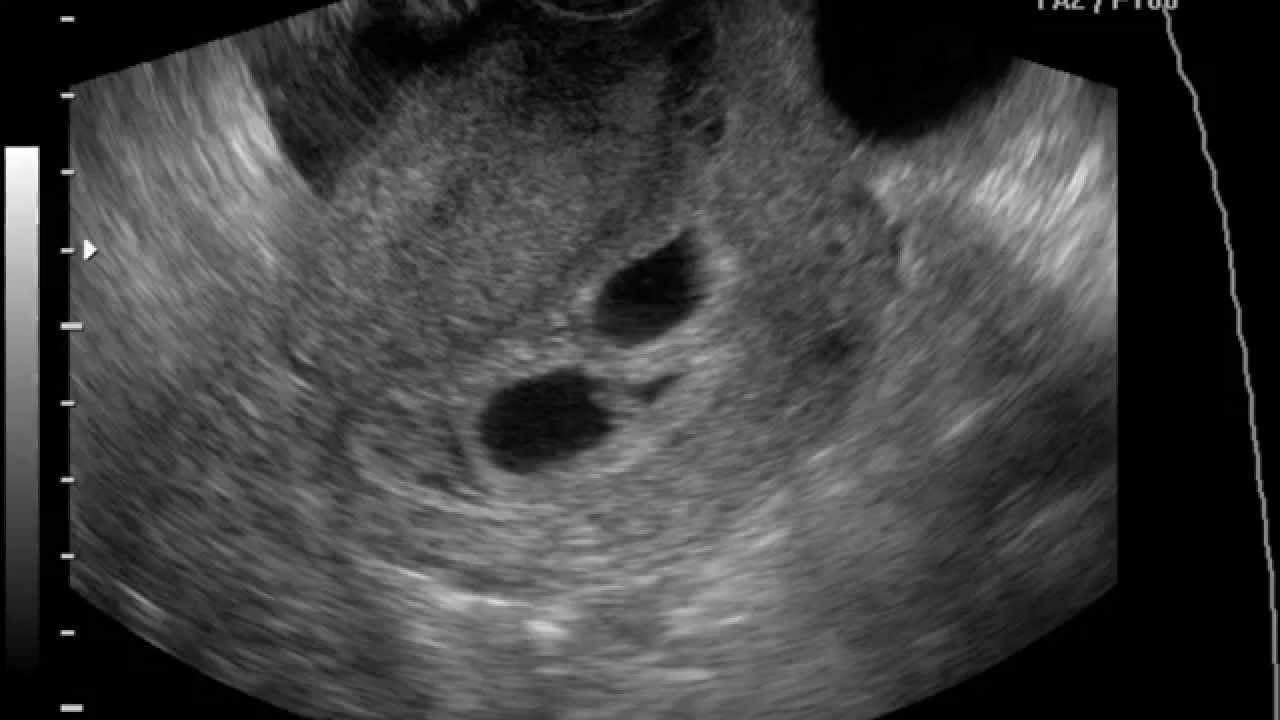

Для подтверждения или опровержения предварительно поставленного диагноза проводится ультразвуковое исследование. По результатам данной процедуры определяется площадь и предлежание плаценты, объем и расположение гематомы, наличие кровяных сгустков.

Также весьма распространенный способ диагностики — это ультразвуковое исследование. УЗИ помогает собрать необходимую информацию о нюансах протекания беременности: развитии эмбриона, сроке, возможных патологиях и отклонениях и т.д. Также мониторинг дает представление о размерах плодного яйца. Многочисленные исследования позволили установить то, какой диаметр характерен для каждого триместра беременности.

Увидеть плодное яйцо на мониторе УЗИ-аппарата можно не раньше, чем спустя неделю после задержки. В этот период оно занимает уже ¼ всего пространства матки и хорошо визуализируется. Что касается эмбриона, то на таком раннем сроке его еще не видно.

УЗИ отслойки плодного яйца

Ранняя диагностика отслойки плодного яйца может спасти беременность от самопроизвольного аборта, который возникает после полного отторжения маткой. Как мы уже сказали, отслойка плодного яйца возникает на начальных сроках беременности, в тот момент, когда яйцо имплантируется в стенки матки и должно быть максимально надежно прикреплено.

Плановое ультразвуковое исследование, которое женщина проходит в первый период беременности, способно выявить отслойку до первых ее симптомных проявлений. На УЗИ сразу станет понятно наличие у вас этой патологии, а при обнаружения можно точно определить ее вид (частичная или полная). В случае, если УЗИ диагностировало у вас отслойку плодного яйца, вам следует лечь в больницу на сохранение и ежедневно находиться под присмотром врачей, пока опасность выкидыша не станет минимальной.